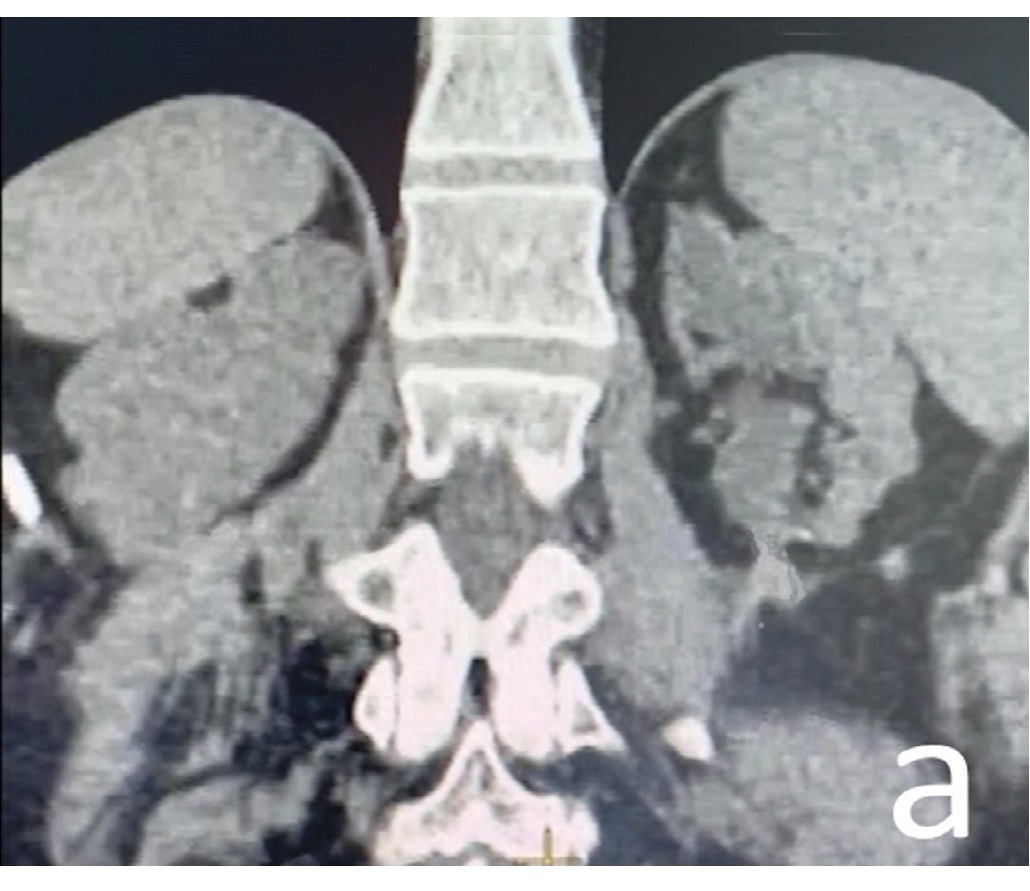

Изображения КТ конкрементов мочевого пузыря